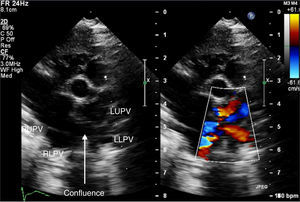

Echocardiography confirmed situs solitus and levocardia. All four pulmonary veins were imaged forming a confluence which opened directly into the right atrium with a mean gradient of 8 mmHg (Figures 1–3). There was no vertical vein and the coronary sinus was normal. Individual pulmonary veins were adequately sized. The ASD was of ostium secundum type, measuring 4.7 mm, with mildly restrictive peak and mean gradients of 5 and 1 mmHg, respectively. Surgical exploration revealed all pulmonary veins draining to the right atrium with a shelf over the opening of the left pulmonary veins. The patient underwent primary sutureless TAPVC repair and closure of the ASD with a tanned pericardial patch, and is doing well.

Supracardiac TAPVC draining into the innominate vein or other channels that connect into the systemic venous atrium is the most common type.2 Classical cardiac-type TAPVCs drain into the coronary sinus. TAPVC with direct connection of the pulmonary veins to the morphological right atrium is exceedingly rare except in the setting of isomeric right atrial appendages.3 In our patient, the muscle-deficient confluence formed by the pulmonary veins draining to the right atrial roof was totally unexpected in the setting of normal atrial situs and normal coronary sinus anatomy. The gradient at the pulmonary venous confluence to the right atrium was flow-related, although the ASD was restrictive. The nomenclature of this defect is itself a point of debate – though anatomically intracardiac, embryologically it drains into the supracardinal venous system, mimicking a supracardiac TAPVC. Computed tomography is useful to delineate the size of individual pulmonary veins and the dimensions of the common chamber and its drainage in TAPVC.4 Magnetic resonance imaging is rarely considered in sick neonates, despite its excellent accuracy, owing to the long duration of the study. However the same information can be obtained fairly reliably in most neonates with TAPVC from careful transthoracic echocardiography. In the case presented, the surgeon was confident of the size of the common chamber and the individual pulmonary veins from the echocardiographic images.